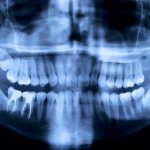

Если причиной воспаления десны является больной зуб, то отек десны может перерасти в периостит (флюс), при этом скапливается гной во рту под десной. Это состояние опасно для жизни, потому что распространение гноя может пойти во внутренние клетчаточные пространства шеи и дна полости рта и осложнится флегмоной. Такие гнойные процессы сопровождаются высокой температурой, слабостью и головокружением, потливостью и ознобом. Поэтому, если вы в городе, обязательно обратитесь к врачу. Если же вы в походе в лесу или горах и врача нет, необходимо принять антибиотики или фторхинолоны широкого спектра действия (например «Рулид», «Авелокс»и по возможности обеспечить эвакуацию силами полиции или службы спасения МЧС в челюстно лицевое отделение больницы.

В детства родители постоянно твердили нам о том, что зубы необходимо чистить тщательно, утром и вечером. То ли из-за возраста или в связи с недостатком времени, многие из нас забыли об этом важном правиле и как оказалось очень зря. Одна из основных причин возникновения кровоточивости десен и как следствие их воспаления, это – неправильная и не постоянная гигиена полости рта. Доказано, что после чистки зубов, уже через 4-5 часов, на поверхности эмали вновь скапливаются вредоносные микроорганизмы, которые постепенно преобразуются в мягкий налет, а затем и в твердый камень. Особенно их распространению содействуют углеводы, поглощая их, бактерии выделяют особые кислоты, которые негативно влияют на здоровье зубов. Из-за налета, десна становятся слабыми и воспаленными, а увеличение зубных отложений приводит к образованию десневых карманов. Сначала у пациента возникает заболевание гингивит, а если воспалительный процесс своевременно не остановить и вылечить, появляется его осложнение пародонтит.

Однако если заболевание прогрессирует, сопровождается повышением температуры, появлением гноя, расшатыванием зубов, то лечение воспаления кармана десны в домашних условиях не только не даст результатов, но может ухудшить ситуацию. В таком случае требуется экстренная помощь квалифицированного стоматолога-пародонтолога, который проведет аппаратное лечение: например, с использованием ультрасовременного прибора «Вектор», работающего на ультразвуке.